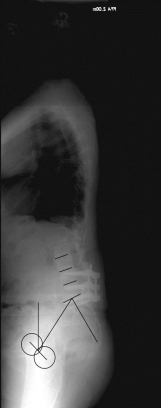

X-ray image before and after surgery. The patient underwent spinal surgery at another hospital and increasingly developed other complaints. The X-ray showed a complete loss of the hollow back and a resulting change in balance. A so-called lordosis operation led to a restoration of a normal hollow back and thus a normal spinal balance and finally to regressive complaints.